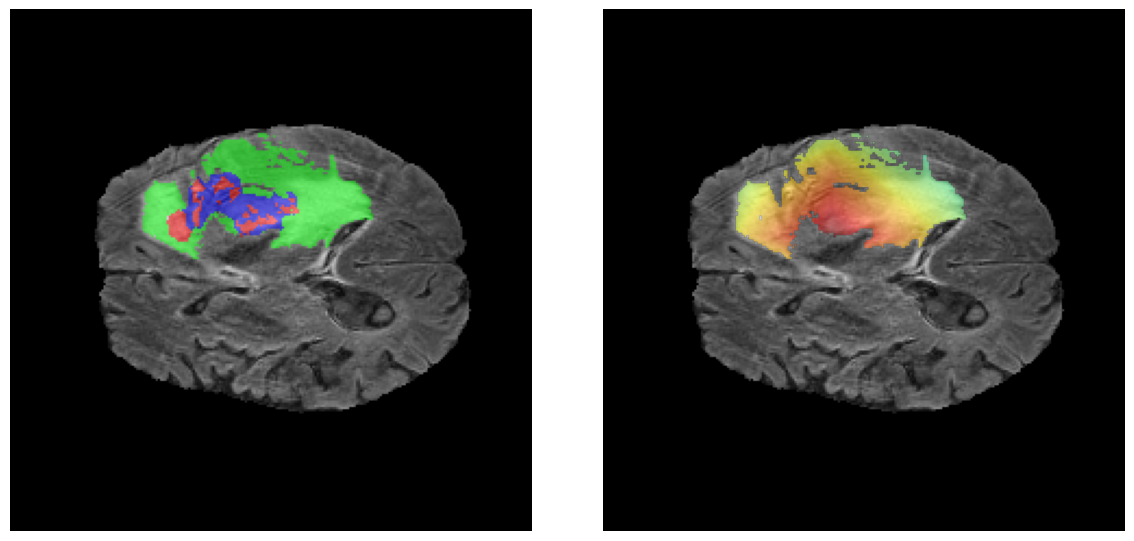

Mapas de Explicabilidad (Grad-CAM++)

Visualización de las regiones de atención del modelo que validan su razonamiento clínicamente relevante

Ejemplos HGG - Atención en Núcleo Necrótico y Tumor Realzado

HGG Grad-CAM++ 1 HGG Grad-CAM++ 2 HGG Grad-CAM++ 3 HGG Grad-CAM++ 4 HGG Grad-CAM++ 5 HGG Grad-CAM++ 6

Los heatmaps muestran que el modelo concentra su atención en las regiones de Tumor Realzado (rojo) y Núcleo Necrótico (azul), características patológicas clave de los gliomas de alto grado.

Validación con IA Explicable

El análisis Grad-CAM++ reveló que el modelo desarrolla automáticamente la capacidad de localizar las regiones tumorales. Para casos HGG, la atención se alinea fuertemente con las regiones de Tumor Realzado (ET) y Núcleo Necrótico (NCR). En contraste, los casos LGG muestran atención más difusa, principalmente concentrada en la región de Edema Peritumoral (ED), lo cual es consistente con la patofisiología conocida de los gliomas.